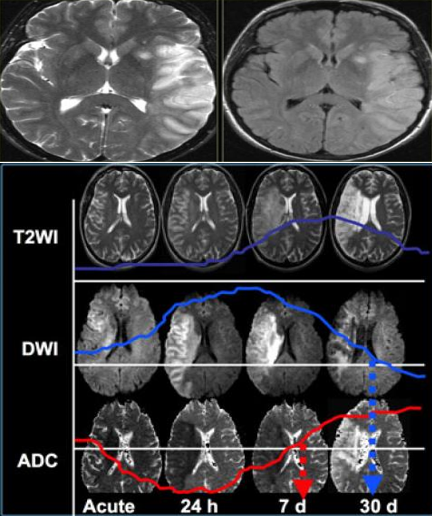

• Nhồi máu cấp phát hiện trên cộng hưởng từ tốt hơn chụp cắt lớp vi tính. Tổn thương nhồi máu nhồi máu phát hiện  trên xung T2 và FLAIR với tín hiệu cao. Các xung này phát hiện 80% các ổ nhồi máu trong 24h đầu. Tuy nhiên có thể biểu hiện bình thường ở giai đoạn tối cấp. Tăng tín hiệu trên T2/FLAIR có giá trị như giảm tỷ trọng trên CT.

• Chuỗi xung khuếch tán DWI là chuỗi xung có độ nhạy cao nhất để phát hiện tổn thương nhồi máu, chỉ trong vòng vài phút sau khi khởi phát triệu chứng vào giai đoạn tối cấp.

• Hình ảnh T2/FLAIR và DWI/ADC thay đổi theo các giai đoạn tiến triển của nhồi máu.